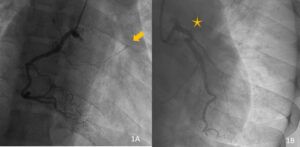

La coronariografía revela una arteria coronaria derecha sin lesiones significativas, observándose relleno colateral hacia la arteria descendente anterior (DA) (imagen 1A), con gran carga trombótica visible (flecha). La inyección selectiva de la coronaria izquierda muestra oclusión completa de la DA desde su ostium (imagen 1B).